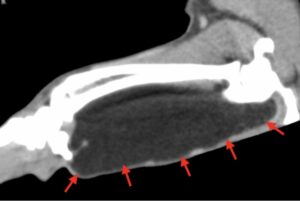

↑ 上の写真は、左前肢の『肘関節より下のCT画像』です。

■ 赤い矢印で示された黒色のエリアが、『筋間脂肪腫』です。

■ 手術では、この黒色のエリアを切除しました。